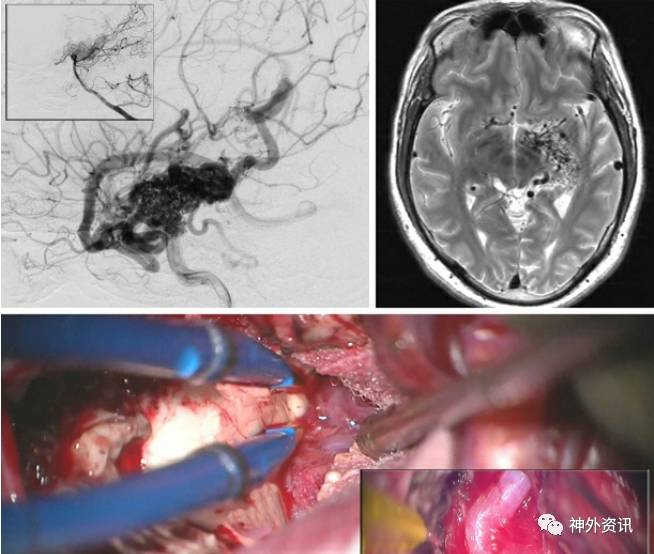

图13. 大型颞叶后内侧AVMs,主要由脉络膜前动脉供血,如图(ICA和椎动脉造影侧位像,上图)。术者采用经皮层、经脑室、经脉络裂的方法(中图)。在穿过颞角的脉络裂中显露脉络膜前动脉 (中图的插图)。AVMs完全游离后,病灶水平的脉络膜前动脉被离断,AVMs去除(下图)。所有浅静脉转为暗蓝色。